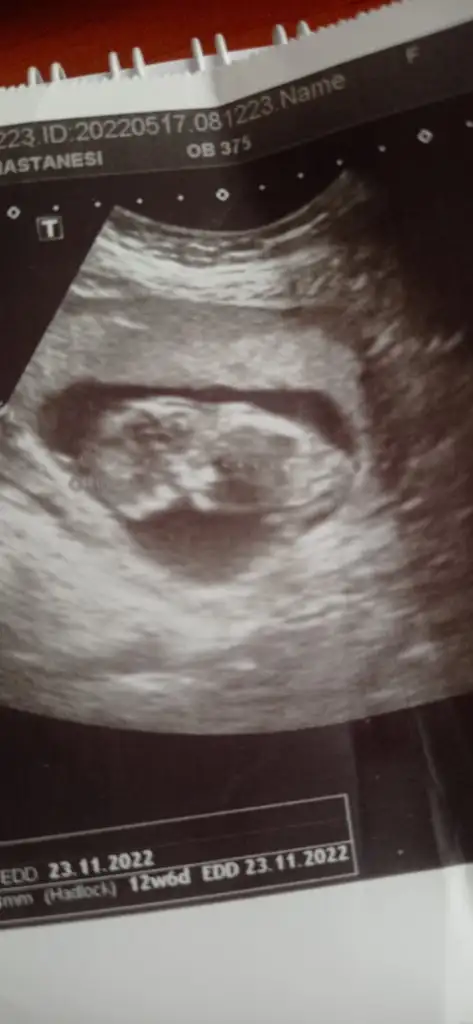

prenses gibi12+6 karından ultrason

Kiz nursu nerdesinkarındansa prenses gibi![]()

ters durmuş prenses